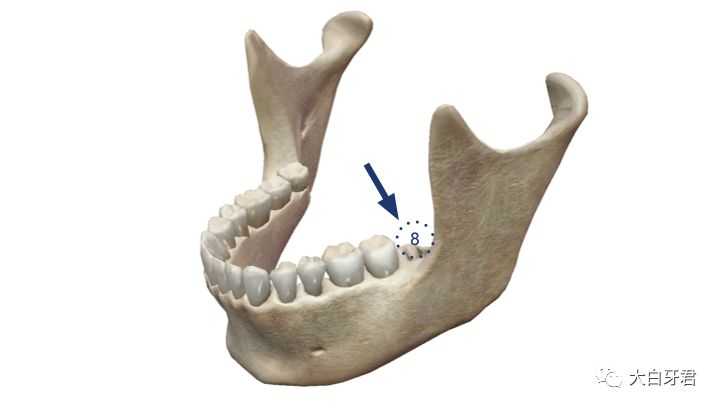

如果缺失的是智齿,也就是位于口腔最深处的第三磨牙,这个牙齿缺失,完全没有镶牙的必要!原因在于:就算有这个第三磨牙,其实也没什么咀嚼功能——一般来说,有第三磨牙(智齿)缺失的,不需要镶牙。

第三磨牙缺失,无需镶牙

第三磨牙缺失,无需镶牙